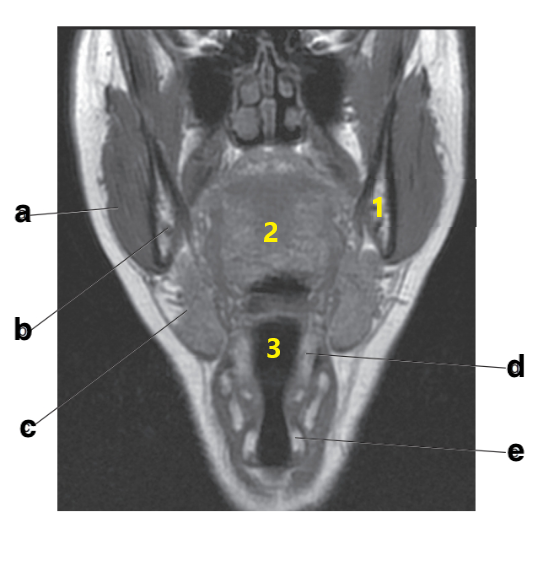

What imaging plane is this?

coronal

Number 2 is on the __________ side of the patient.

lateral

What anatomy is # 3?

fibula

Where is the tibial plateau?

3 and 4